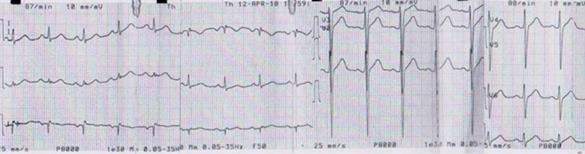

Hombre de 53 años, diabético tipo 2 en tratamiento con metformina, estresado. En la semana previa presentó ángor a esfuerzos moderados acompañado de síndrome neurovegetativo, por lo que fue visto en policlínica, realizándose electrocardiograma (ECG) que no evidenció alteraciones isquémicas, otorgándose alta a domicilio. El 18 de marzo de 2018 reitera episodio de mayor intensidad, por lo que consulta a unidad de emergencia móvil. Se realiza ECG que evidencia supradesnivel del segmento ST en cara inferior (figura 1).

Figura 1: Electrocardiograma del paciente al ingreso. Imagen de infarto agudo de miocardio inferior evolucionado.